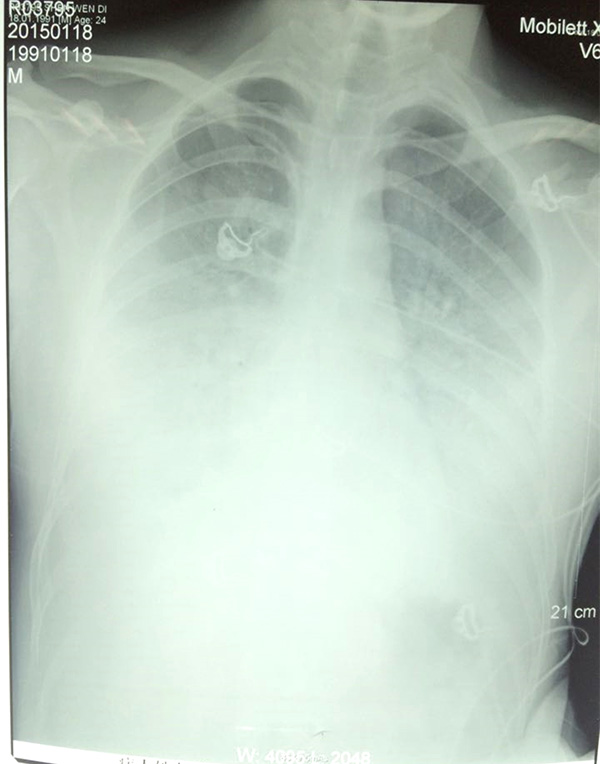

當天下午,醫生通過會診,發現陶園的雙肺均有炎癥,出現“白肺”跡象,這說明此時肺部已經無法完成氧氣交換。而“白肺”最常見的病因是感染,其次是彌漫性肺泡出血綜合征、急性呼吸窘迫綜合征等。

陶園的肺部CT

1月18日,陶園使用氣管插管接呼吸機輔助呼吸;1月19日,病情持續惡化,白肺進一步加重,CT上整個肺部幾乎都是白色;1月20日,三院專家和市第一人民醫院兩位專家以及來自上海第二軍醫大學附屬長海醫院的專家經過會診,決定最后使用CRRT(體外血液凈化以替代受損的腎功能)和ECOM(體外血液循環替代受損的心肺功能)試一下。